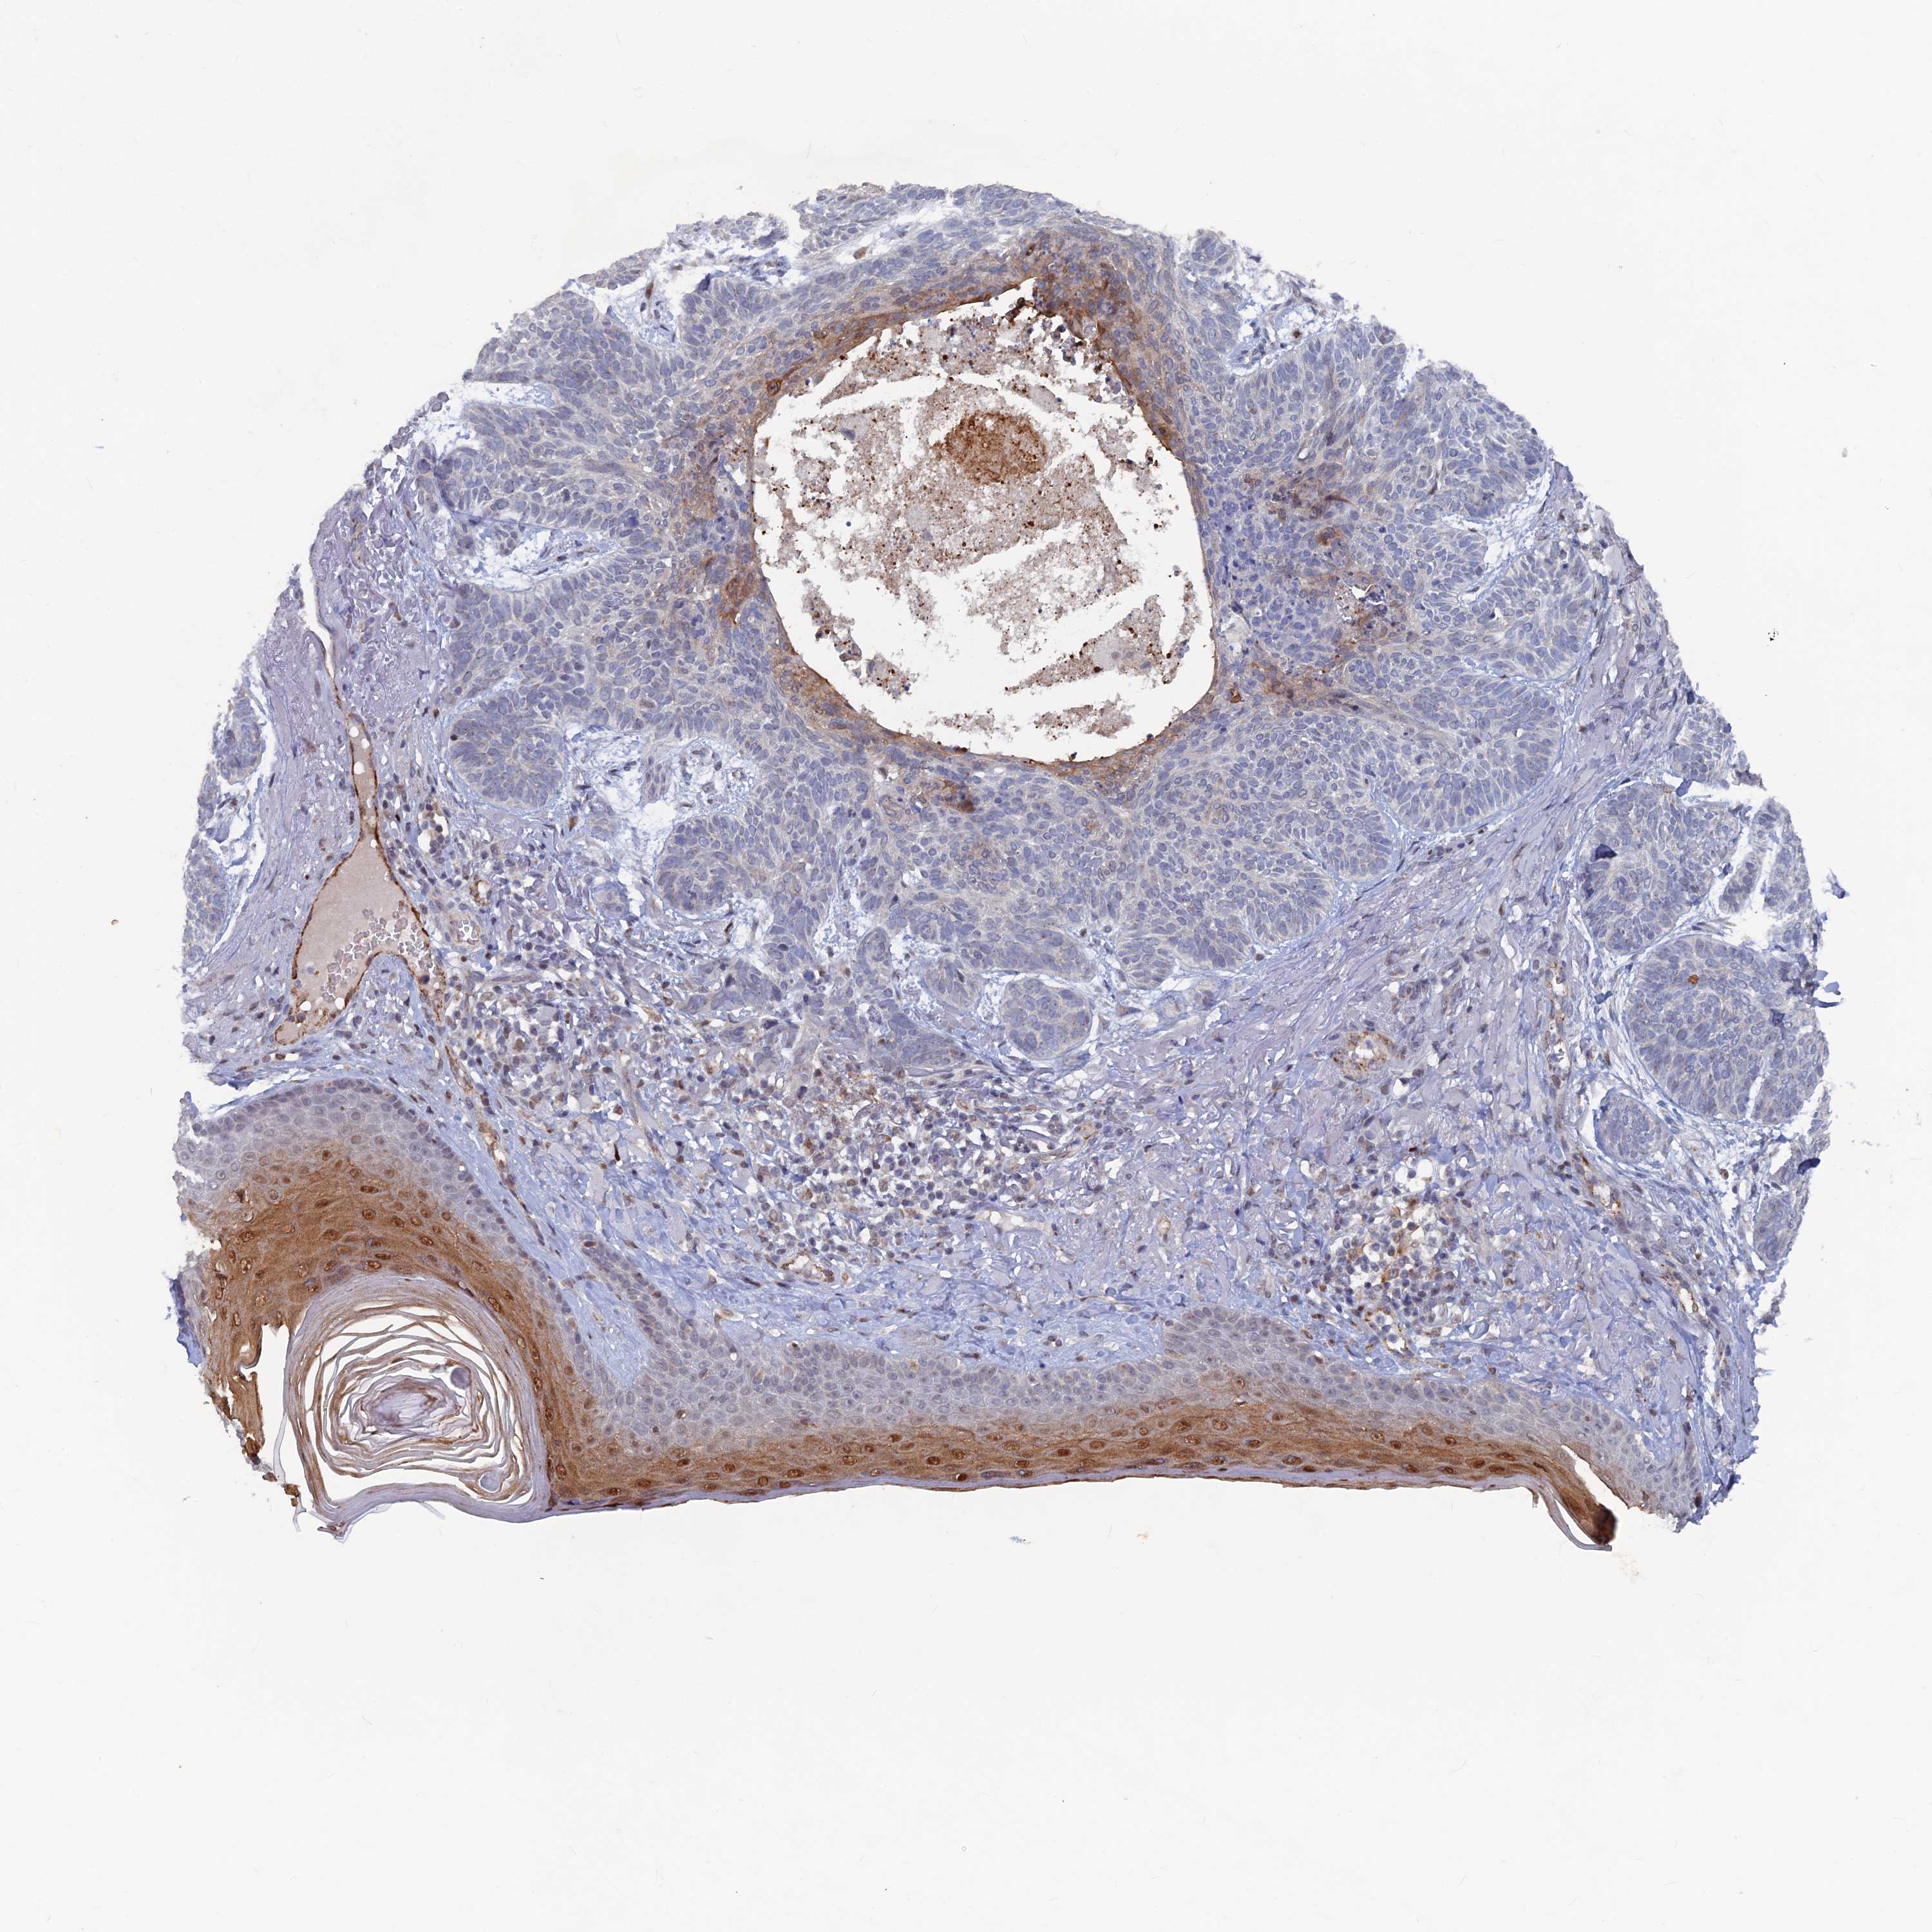

Basal cell and squamous cell cancer

SKIN CANCER - Protein expressioni

A mouse-over function shows sample information and annotation data. Click on an image to view it in a full screen mode. Samples can be filtered based on level of antibody staining by selecting one or several of the following categories: high, medium, low and not detected. The assay and annotation is described here.

Each image is clickable and will lead to virtual microscopy that enables deeper exploration of all samples and also displays staining intensity scores, fraction scores and subcellular localization as well as patient and tissue information for each sample.

Antibody HPA042212

Antibody HPA042456

Squamous cell carcinoma, NOS